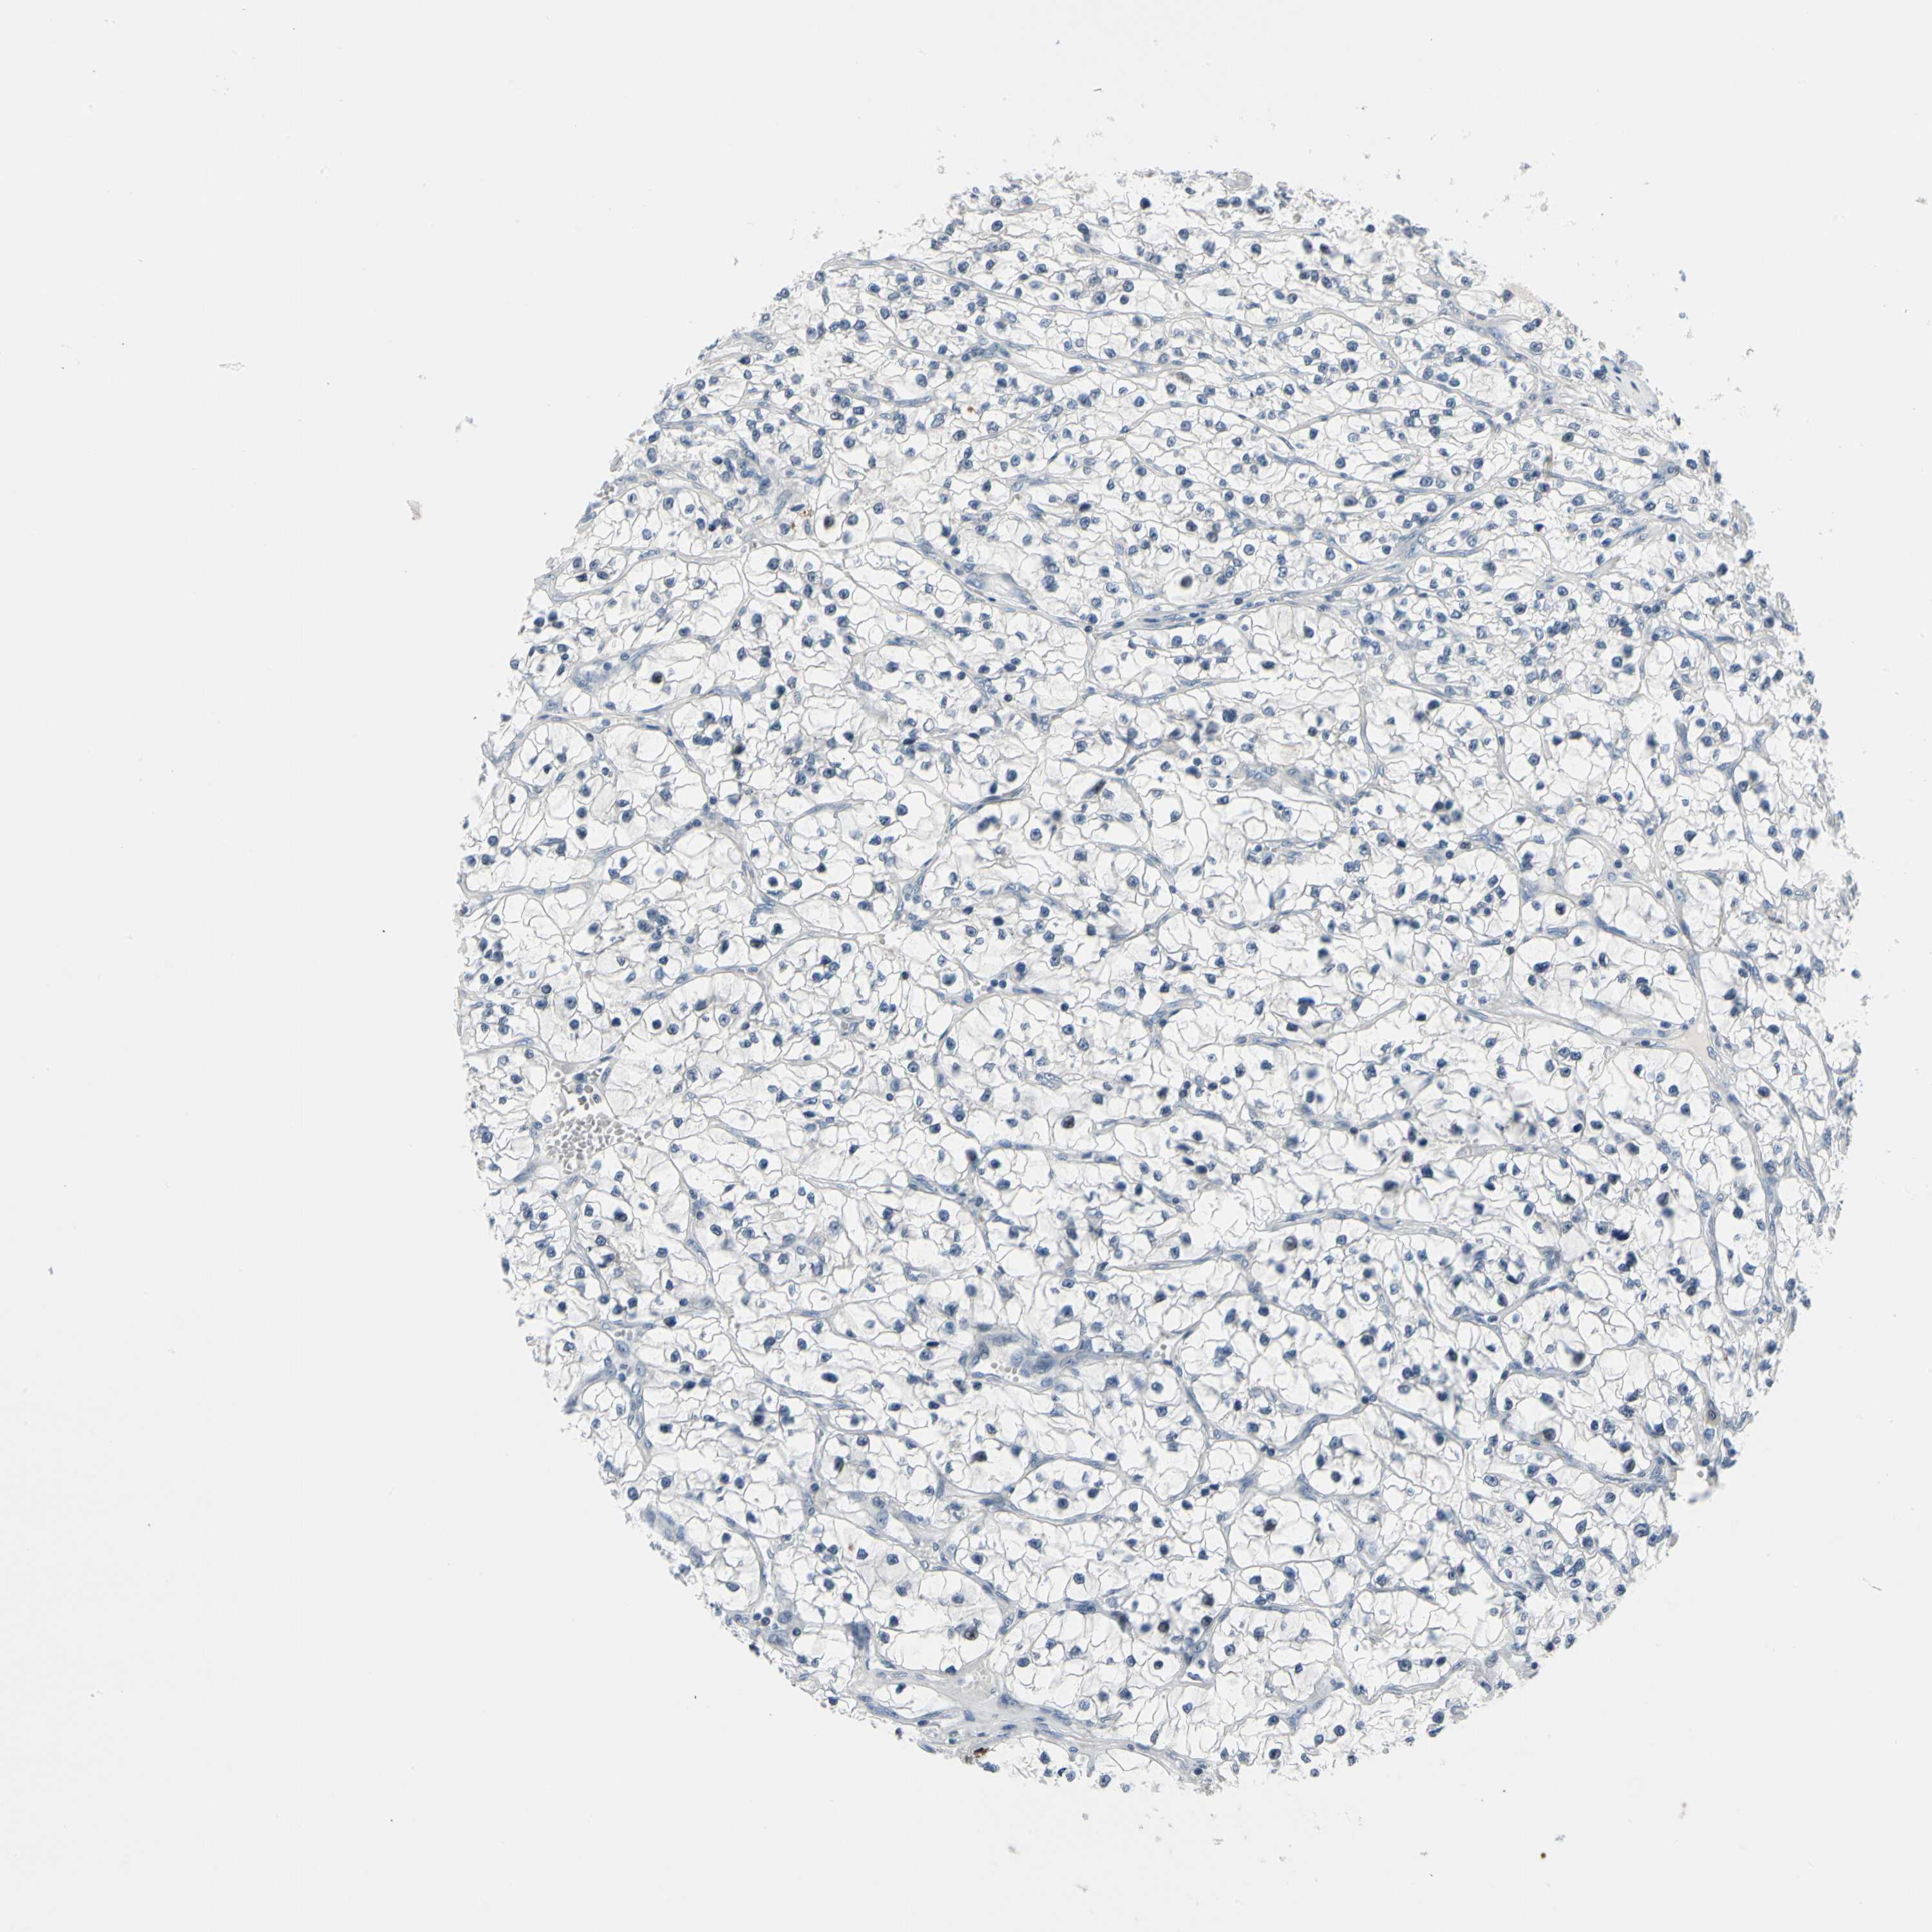

CANCER RENAL CANCER Show tissue menu

KICH TCGA KIRC TCGA KIRC VALIDATION KIRP TCGA PROTEIN RCC CPTAC PROTEIN EXPRESSION